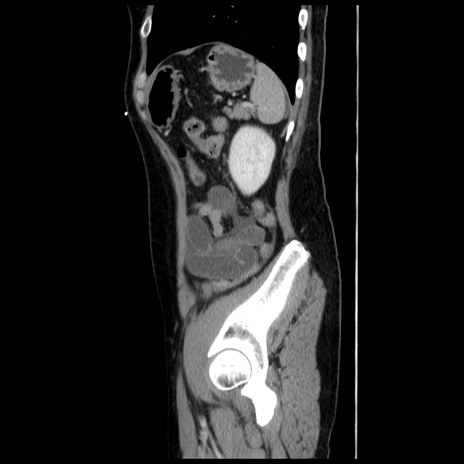

症例10(矢状断像)

【症例】 50歳代女性

【主訴】 腹痛

【現病歴】前日生レバーを食べた。今朝に排便あり。 昼前に突然発症の腹痛を生じ、当院救急外来を受診した。

【既往歴】 子宮筋腫にてで子宮全摘後

【身体所見】 意識清明、腹部:平坦、軟、下腹部やや左を中心に圧痛・反跳痛あり、筋性防御あり

【データ】WBC 7800、CRP 0.07